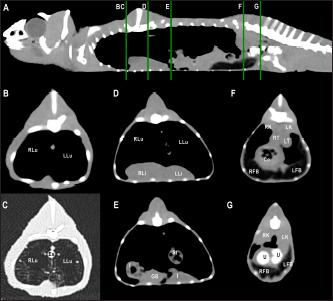

Fig. 7. Sagittal right paramedian postcontrast CT image displayed in soft tissue window (A) and selected corresponding transverse images represented as green line section, displayed in soft tissue window, at the level of intestines (B), fat bodies and ovaries (C), and urinary bladder (D) in a female veiled chameleon (C. calyptratus). H, heart; GB, gallbladder; arrow, enhancement of the gallbladder; RLu, right lung; LLu, left lung; Ov, ovaric follicles; Co, colon; I, intestine; RFB, right fat body; LFB, left fat body; RAS, right air sac; LAS, left air sac; arrowhead, ovarian vessels; #, caudal vein; *, Li, liver; kidneys; U, urinary bladder; RF, right femur; LF, left femur; PB, pelvic bone.

Fig. 8. Sagittal precontrast CT image displayed in soft tissue window (A) and selected corresponding transverse images represented as green line section, displayed in soft tissue window at the level of the liver (B), ovaries (C), and kidneys/fat bodies (D) in a female panther chameleon (F. pardalis). E, eggs; RLi, right liver lobe; LLi, left liver lobe; ROv, right ovary; LOv, left ovary; RK, right kidney; LK, left kidney; LFB, left fat body.